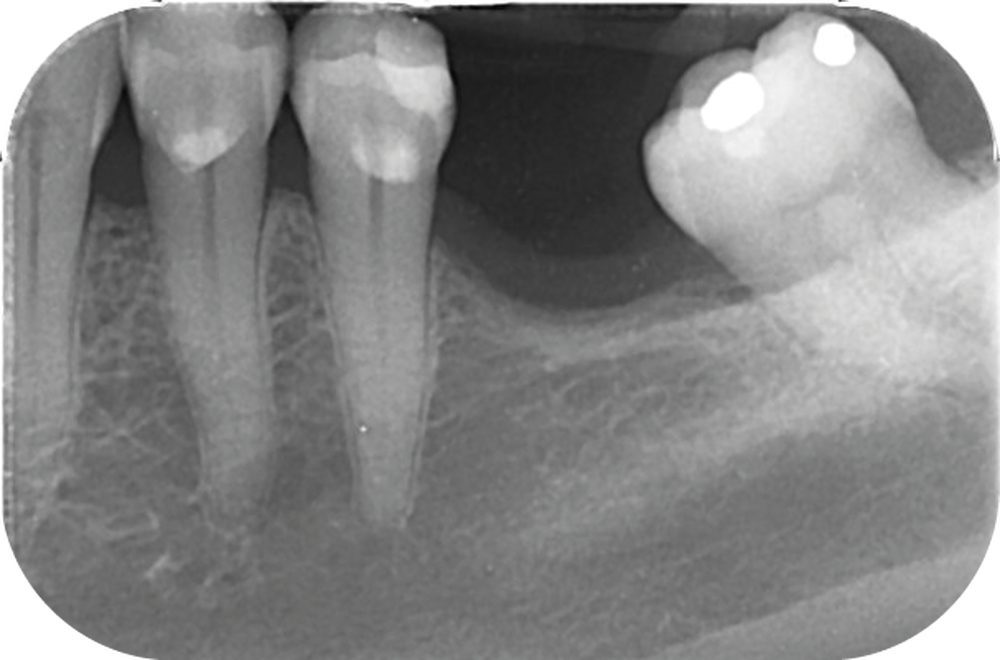

La perte d’une ou plusieurs dents entraîne la perte des points de contact, responsables de la stabilité et de la continuité de l’arcade. Par conséquent, une avulsion a pour première conséquence la migration ou la version d’une ou plusieurs dents distales (fig. 1 et 2). Cela est vrai en antérieur comme en postérieur.

Cette version, quand elle se produit, modifie les espaces interdentaires et complique l’hygiène proximale des patients. Des caries peuvent alors se développer en interproximal sans que cela soit forcément visible à l’examen visuel (fig. 3 et 4). Les radios de type bite-wing (rétro-coronaires) prennent alors tout leur sens (fig. 5 et 6).

La version des dents distales peut aussi avoir des conséquences parodontales désastreuses : sur un parodonte réduit, une hypermobilité peut se développer, une poche parodontale peut aussi apparaître. Chez un patient parodontal, un « effet domino » est possible, des extractions non compensées diminueront donc le pronostic des dents restantes (fig. 7 à 9).